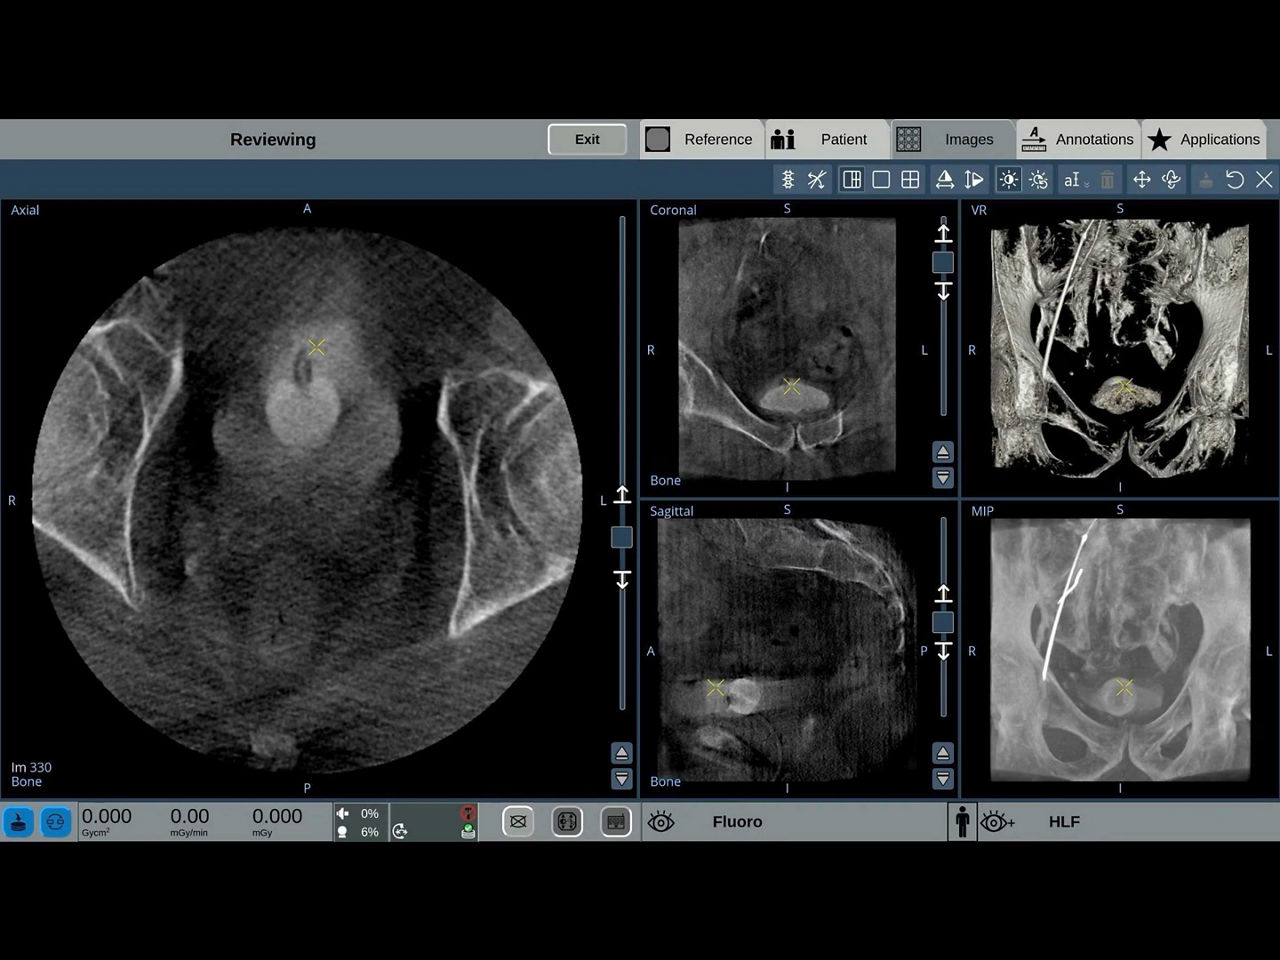

When visual confirmation during a procedure is desired, the

OEC 3D can provide 3D volumes with five perspectives.

Analyze CT-like images with the OEC 3D Volume Viewer which includes Multi-Oblique, Area Measure, Window Level/Window Width, rotate, zoom, and more for quick and comprehensive visualization.